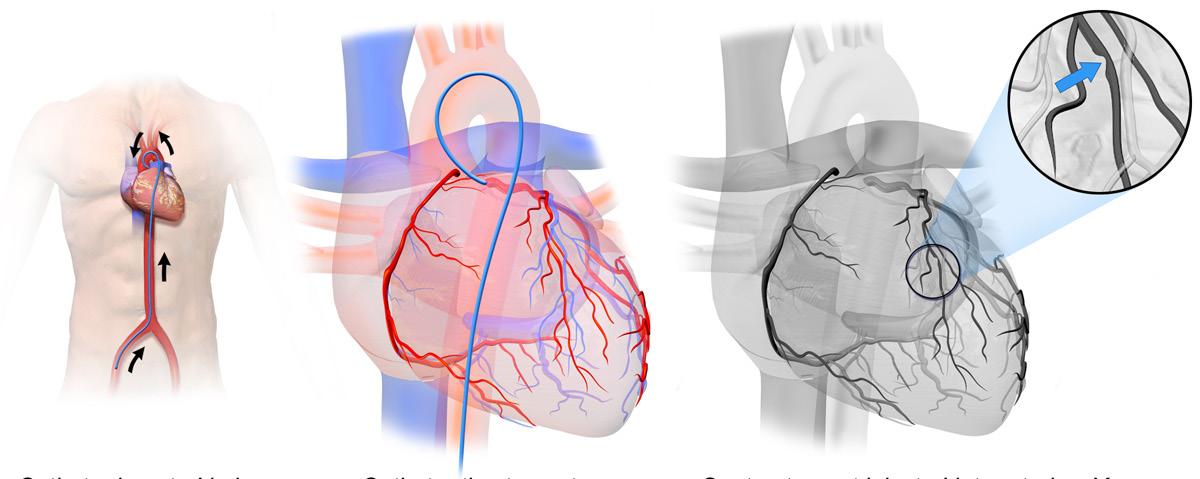

Imagem didática de um cateterismo das artérias coronárias, onde podemos perceber que o cateter inserido no vaso da coxa (imagem A) vai até o coração para realizar imagens (imagens B e C) ou procedimentos.

O cateterismo cardíaco é um procedimento diagnóstico que desempenha um papel essencial na identificação e avaliação de doenças cardíacas Esse exame envolve a inserção de um cateter — um tubo fino e flexível — através de um vaso sanguíneo, geralmente na virilha ou no pulso, até o coração.

Ao injetar um meio de contraste e utilizar radiografias em tempo real, os médicos podem visualizar as artérias coronárias e identificar obstruções ou estreitamentos que possam comprometer o fluxo sanguíneo para o coração. Além disso, o cateterismo cardíaco permite a avaliação da função cardíaca e a medição das pressões dentro das câmaras do coração e nas artérias pulmonares, sendo particularmente útil no diagnóstico e tratamento de condições como insuficiência cardíaca, doenças valvares e hipertensão pulmonar.